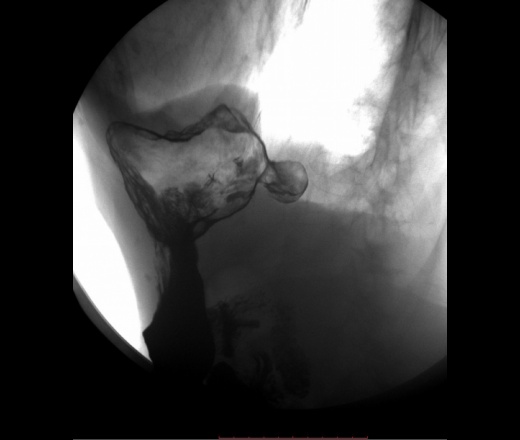

Локализация харатерная для дивертикула желудка(задняя стенка свода), тип дивертикула нехарактерный по механизму формирования, тут по типу пульсионного, характерен тракционный механизм, за счёт явлений перипроцесса. Может быть я и неправ.

"Дивертикулы желудка Дивертикулы желудка (ДЖ) встречаются очень редко, случайно они обнаруживаются в 0,02% случаев аутопсий [57]. ДЖ имеют грушевидную, реже – овальную форму, размеры их обычно небольшие, слизистая оболочка чаще не изменена. Юкстакардиальные ДЖ составляют до 75% всех ДЖ. Они наиболее часто локализуются в области пищеводно-желудочного соединения, обычно на малой кривизне желудка, чаще на задней стенке, что объясняют особенностью расположения мышечных пучков собственного мышечного слоя стенки желудка. ДЖ наиболее часто встречаются в среднем возрасте и имеют размеры от 1 до 3 см в диаметре [58, 59]. Интрамуральные или частичные ДЖ формируются путем выпячивания слизистой оболочки через мышечный слой. Такие ДЖ чаще встречаются в препилорической зоне, обычно в области большой кривизны желудка [60]. При проведении эндоскопии или бариевого контрастирования стриктуры пептические язвы и другие деформации могут иметь сходство с препилорическими ДЖ."http://helpiks.org/3-80531.html

Дивертикулы желудка (ДЖ) встречаются очень редко, случайно они обнаруживаются в 0,02% случаев аутопсий [57]. ДЖ имеют грушевидную, реже – овальную форму, размеры их обычно небольшие, слизистая оболочка чаще не изменена.

Юкстакардиальные ДЖ составляют до 75% всех ДЖ. Они наиболее часто локализуются в области пищеводно-желудочного соединения, обычно на малой кривизне желудка, чаще на задней стенке, что объясняют особенностью расположения мышечных пучков собственного мышечного слоя стенки желудка. ДЖ наиболее часто встречаются в среднем возрасте и имеют размеры от 1 до 3 см в диаметре [58, 59]. Интрамуральные или частичные ДЖ формируются путем выпячивания слизистой оболочки через мышечный слой. Такие ДЖ чаще встречаются в препилорической зоне, обычно в области большой кривизны желудка [60]. При проведении эндоскопии или бариевого контрастирования стриктуры пептические язвы и другие деформации могут иметь сходство с препилорическими ДЖ."http://helpiks.org/3-80531.html